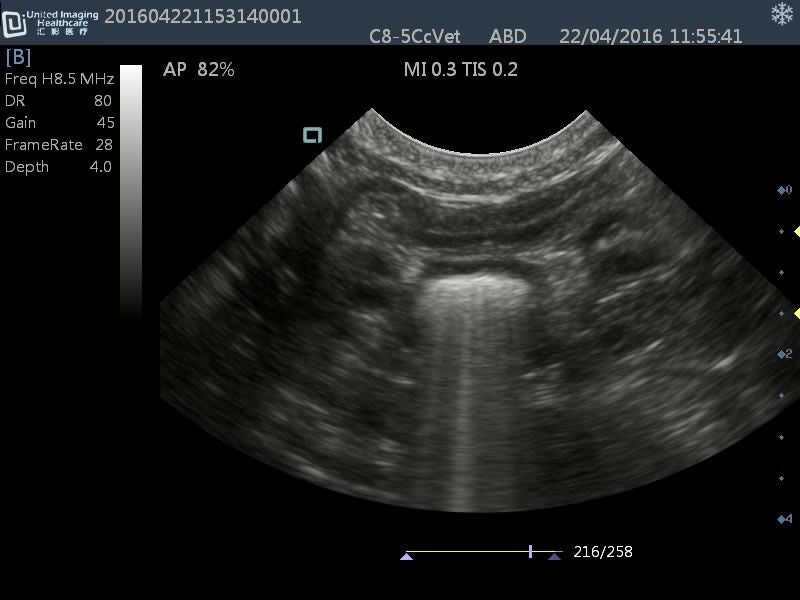

Micro-convex(R15): C8-5Cc

- Application: General small abdomen and cardiac

- Equine musculoskeletal and abdomens

- Number of element: 80

- Center frequency: 6.5MHz

- Working frequencies: 5 – 9MHz